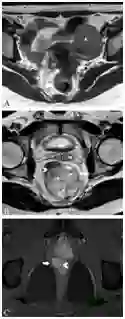

T2加权像粘液性肿瘤呈明显高密度信号,外周蕾丝样增强。MRI检查缺点如下:粘液性肿瘤弥漫性浸润生长已传播至肠壁外,而肠壁解剖结构仍完整;放化疗后即便已无肿瘤、唯留粘液湖时,粘液性肿瘤仍倾向于保持高密度信号(图8);粘液性肿瘤T2加权像呈水样高密度信号,而周围盆腔脂肪也是高密度信号,因此薄层高分辨非压脂轴位T2加权像很易漏诊,此时需调整MRI参数,采用T2加权压脂像抑制脂肪信号,或非压脂轴位T2加权像采用二种不同高回波时间(TE)检测肿瘤,因为周围盆腔脂肪产生二种不同的密度信号(图9)。

图9  直肠粘液腺癌。TE 80ms(9A)和120ms(9B)轴位T2加权像显示直肠腔内粘液腺癌不同的高密度信号(星号),右侧肠壁(箭头)和左侧直肠系膜(长箭头),二种TEs信号差别有助于肿瘤检测。9C显示轴位T2加权压脂像,方便检测肿瘤(星号)和肿瘤播散(长箭头)。